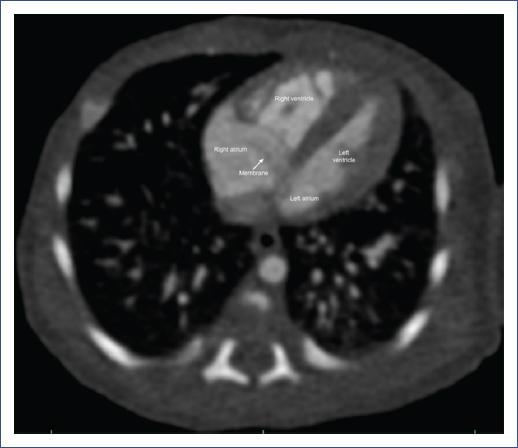

Cardiac magnetic resonance imaging (MRI) revealed a complete CTD with an ASD and concordant atrioventricular and ventriculoarterial connections (Fig. 2).

Figure 2 Cardiac magnetic resonance imaging, sagittal plane, showing a membrane (white arrow) in the right atrium.